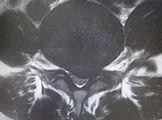

腰椎分離症のCT。突起間部の一部に骨折がみえる。